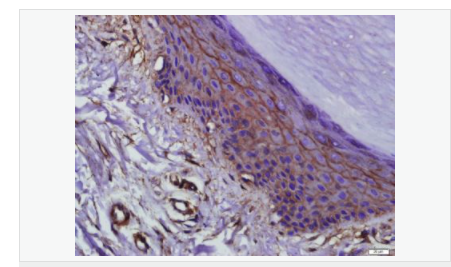

| 產(chǎn)品應(yīng)用 | WB=1:500-2000 ELISA=1:5000-10000 IHC-P=1:100-500 IHC-F=1:100-500 Flow-Cyt=1μg/Test ICC=1:100 IF=1:100-500 (石蠟切片需做抗原修復(fù)) not yet tested in other applications. optimal dilutions/concentrations should be determined by the end user. |

| 產(chǎn)品介紹 | This gene encodes an integral membrane protein which is located at tight junctions. This protein may be involved in the formation and maintenance of the tight junction. The possibility of several alternatively spliced products has been suggested but the full nature of these products has not been described. [provided by RefSeq]. Function: May play a role in the formation and regulation of the tight junction (TJ) paracellular permeability barrier. Subunit: Interacts with TJP1/ZO1 and with VAPA. Subcellular Location: Membrane; Multi-pass membrane protein. Cell junction, tight junction. Tissue Specificity: Localized at tight junctions of both epithelial and endothelial cells. Highly expressed in kidney. Not detected in testis. Post-translational modifications: Phosphorylated upon DNA damage, probably by ATM or ATR. Dephosphorylated by PTPRJ. May be phosphorylated by PKC during translocation to cell-cell contacts. Similarity: Belongs to the ELL/occludin family. Contains 1 MARVEL domain. SWISS: Q16625 Gene ID: 100506658 Database links: Entrez Gene: 18260 Mouse Entrez Gene: 100506658 Human Omim: 602876 Human SwissProt: Q16625 Human SwissProt: Q61146 Mouse Unigene: 592605 Human Unigene: 4807 Mouse Unigene: 31429 Rat Important Note: This product as supplied is intended for research use only, not for use in human, therapeutic or diagnostic applications. |